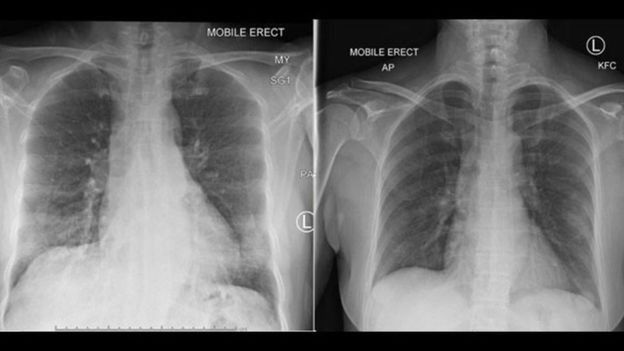

زنی ٤٧ ساله اهل ووهان در استرالیا به بیمارستان مراجعه میکند و بستری میشود. او مبتلا به کرونای ٢٠١٩ خفیف تا متوسط بود. پروفسور کدزیرسکا و همکارانش "کل واکنش سیستم ایمنی" او را زیر نظر گرفتند.

علائم بیمار "در روز سیزدهم کاملا بهبود یافتند" و پادتنها (ایمونگلوبولینهای G و M) تا هفت روز بعد یعنی روز بیستم در پلاسمای خون او "مرتب افزایش یافتند."